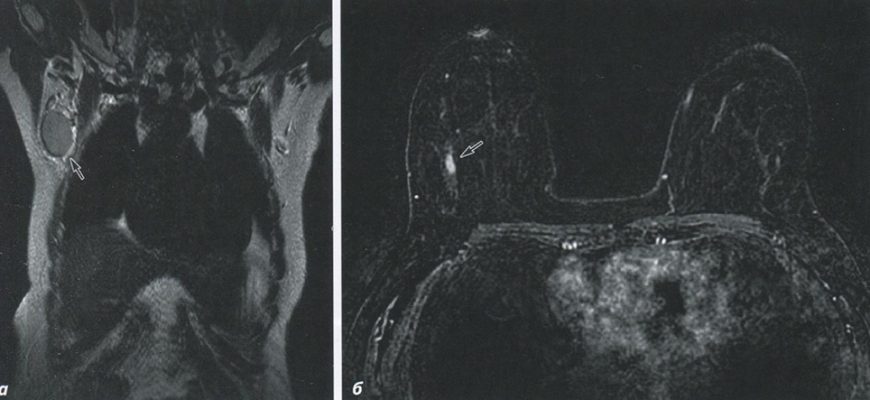

Новые подходы к визуализации опухолей (МРТ с контрастом) В современном мире диагностика опухолей становится все более сложной и многогранной задачей.

Независимо от цели: использование новых контрастных агентов для МРТ и их влияние на диагностику В современном мире медицинской визуализации магнитно-резонансная